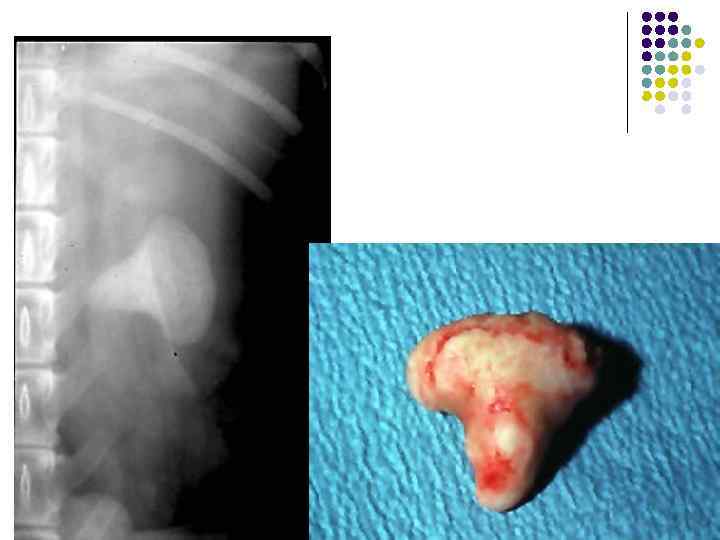

Опухоль брыжейки кишечника

Объёмное образование в брюшной полости